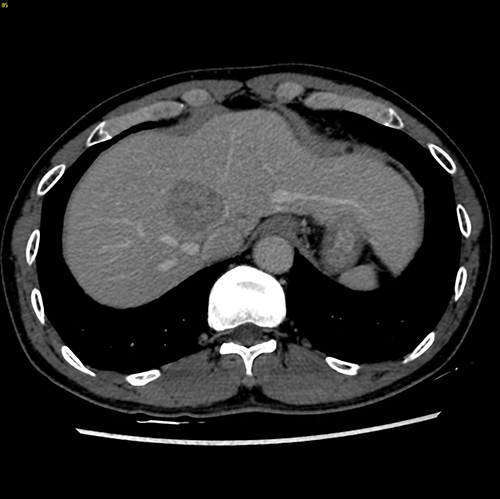

S8肝癌---改良肝中叶切除(3D打印)